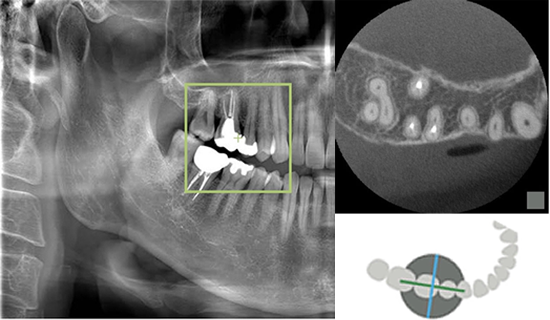

シミュレーションソフトを用いて、

サージカルガイドを作り、CTで精密検査し、

質の高いインプラント治療を安心・安全に行っております。